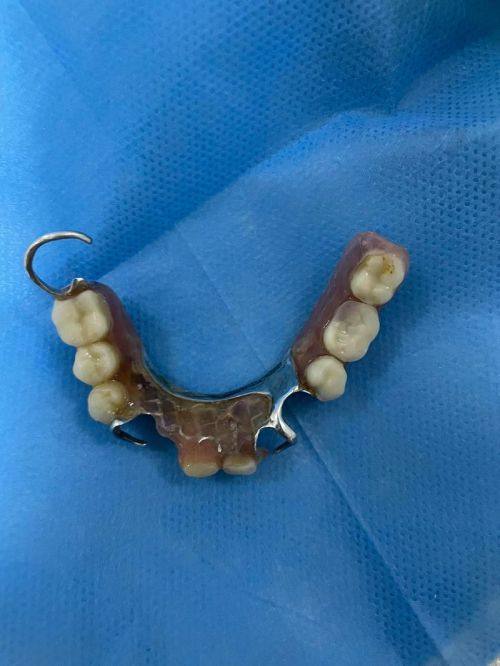

活动义齿一般多少钱一颗费用?2026年最新价格揭秘! 文章揭秘2026年活动义齿最新价格。通常镶活动假牙一颗1000 - 3000元,不同类型费用有别。如隐形义齿1000 - 1200元,便宜但寿命短、咀嚼差;钴铬合金等1500 - 2000元,强度好、使用久;纯钛基托2000 - 3000元,舒适美观。此外,地区、医院等级和医生水平也影响价格,选义齿要综合考量。 活动义齿 2026年03月04日 0 点赞 0 评论 7 浏览

活动义齿哪种最舒服还不伤害基牙?揭秘3种最佳选择! 本文围绕“活动义齿哪种最舒服还不伤害基牙”展开。首先强调了活动义齿舒适与护基牙的重要性,接着介绍了纯钛金属基托活动义齿等三种义齿的特点,包括舒适度、对基牙的影响、价格等。还给出选择建议,要考虑口腔状况、经济因素,并听取医生建议。最后提醒佩戴后注意适应期、清洁和饮食,综合考量选适合自己的义齿。 活动义齿 2026年03月04日 0 点赞 0 评论 12 浏览

补一颗活动义齿多少钱?揭秘真实费用与选择技巧! 本文围绕补一颗活动义齿的费用及选择技巧展开。费用大致在100 - 300元,受材料、修复难易、医院级别、当地经济等因素影响。不同材料义齿各有特点和价格区间。选择时要综合自身情况,选正规机构,多对比。此外,后期维护有成本,需正确佩戴清洁。提醒大家综合考量价格、质量和舒适度,必要时咨询医生。 活动义齿 2026年03月04日 0 点赞 0 评论 7 浏览